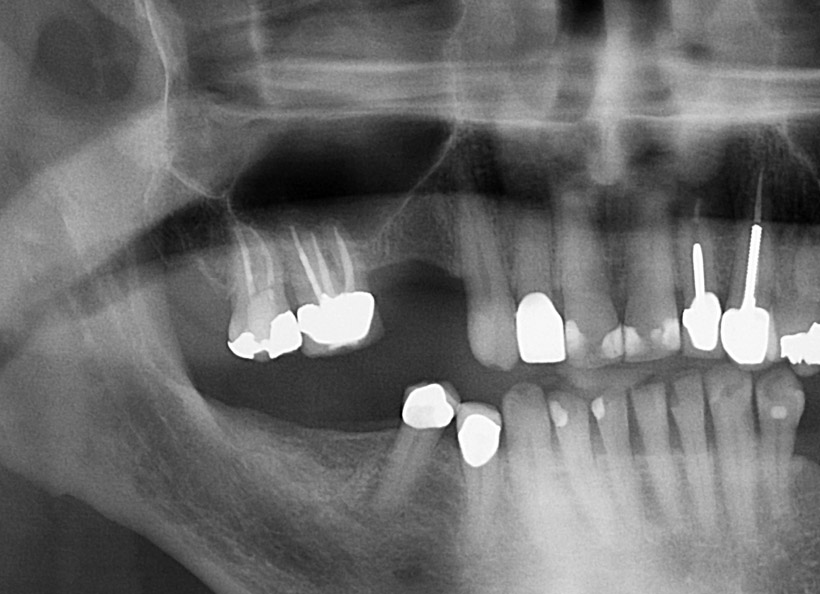

Radiografia digitală panoramică sau Ortopantomografia este radiografia digitală care ne oferă o imagine de ansamblu la toţi dinţii din cavitatea bucală, inclusiv sinusurile maxilare şi aticulaţiile temporo-mandibulare. Este indicată la începerea unui tratament stomatologic pentru a vedea zonele mai greu accesibile ale dinţilori, retracţiile osoase, existenţa şi adâncimea pungilor parodontale, existenţa dinţilor incluşi, etc.

Radiografia digitală panoramică O.P.T. pentru sinusurile maxilare